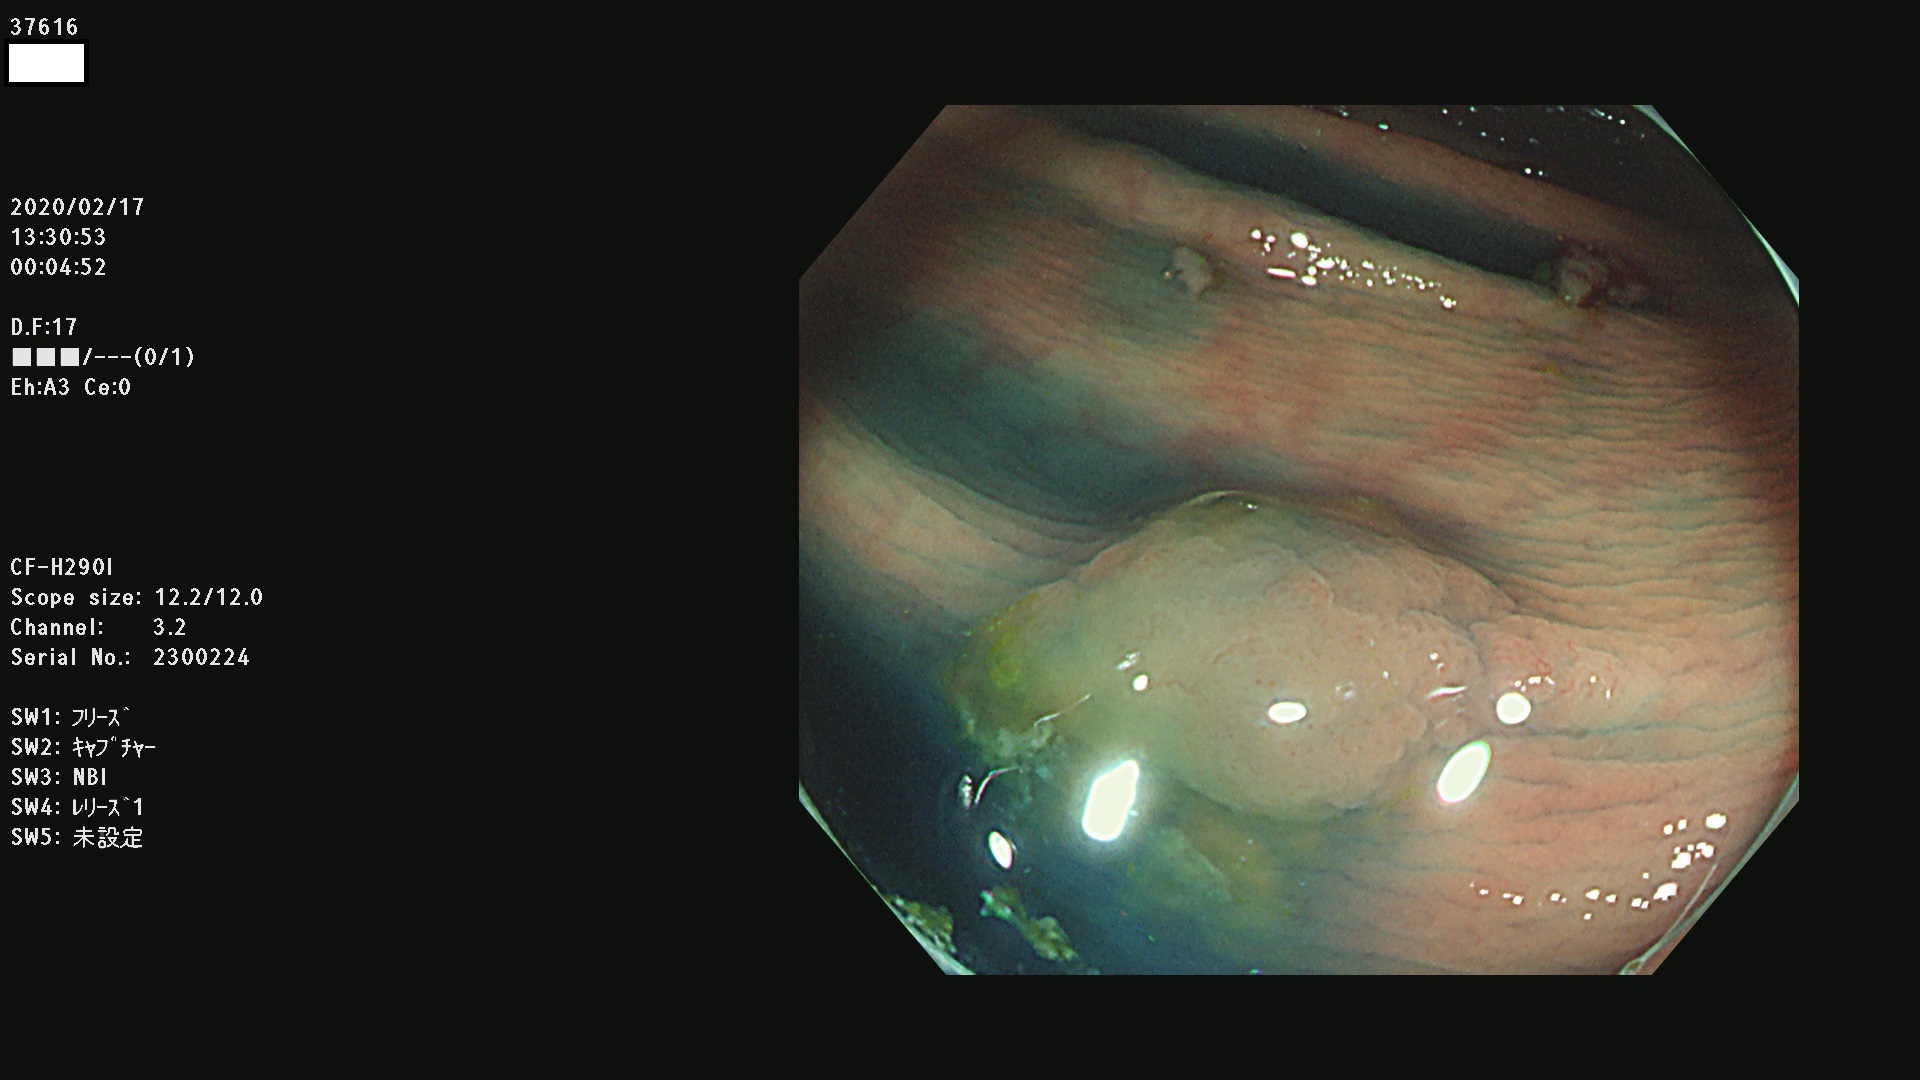

37600 37601 37602 37603 37604 37605 37606 37607 37608 37612 37614 37616 37618 37619 37620 37621 37622(SSAPのみ) 37623(SSAPのみ) 37624 37626 37627 37628 37629 37632 37633 37635 37636(SSAPのみ) 37639 37640 37641 37642 37643 37644 37647(SSAPのみ) 37648 37649 37650 37652 37653 37655 37657 37659 37660 37662 37664 37666 37668(SSAPのみ) 37670 37671 37672 37676 37677 37678 37679 37680 37682 37684 37685(SSAPのみ) 37686 37687 37688 37689 37690 37691 37692(SSAPのみ) 37693 37694 37695 37696 37697 37699

発見困難で危険性の高い平坦型病変(上記100名より抽出)